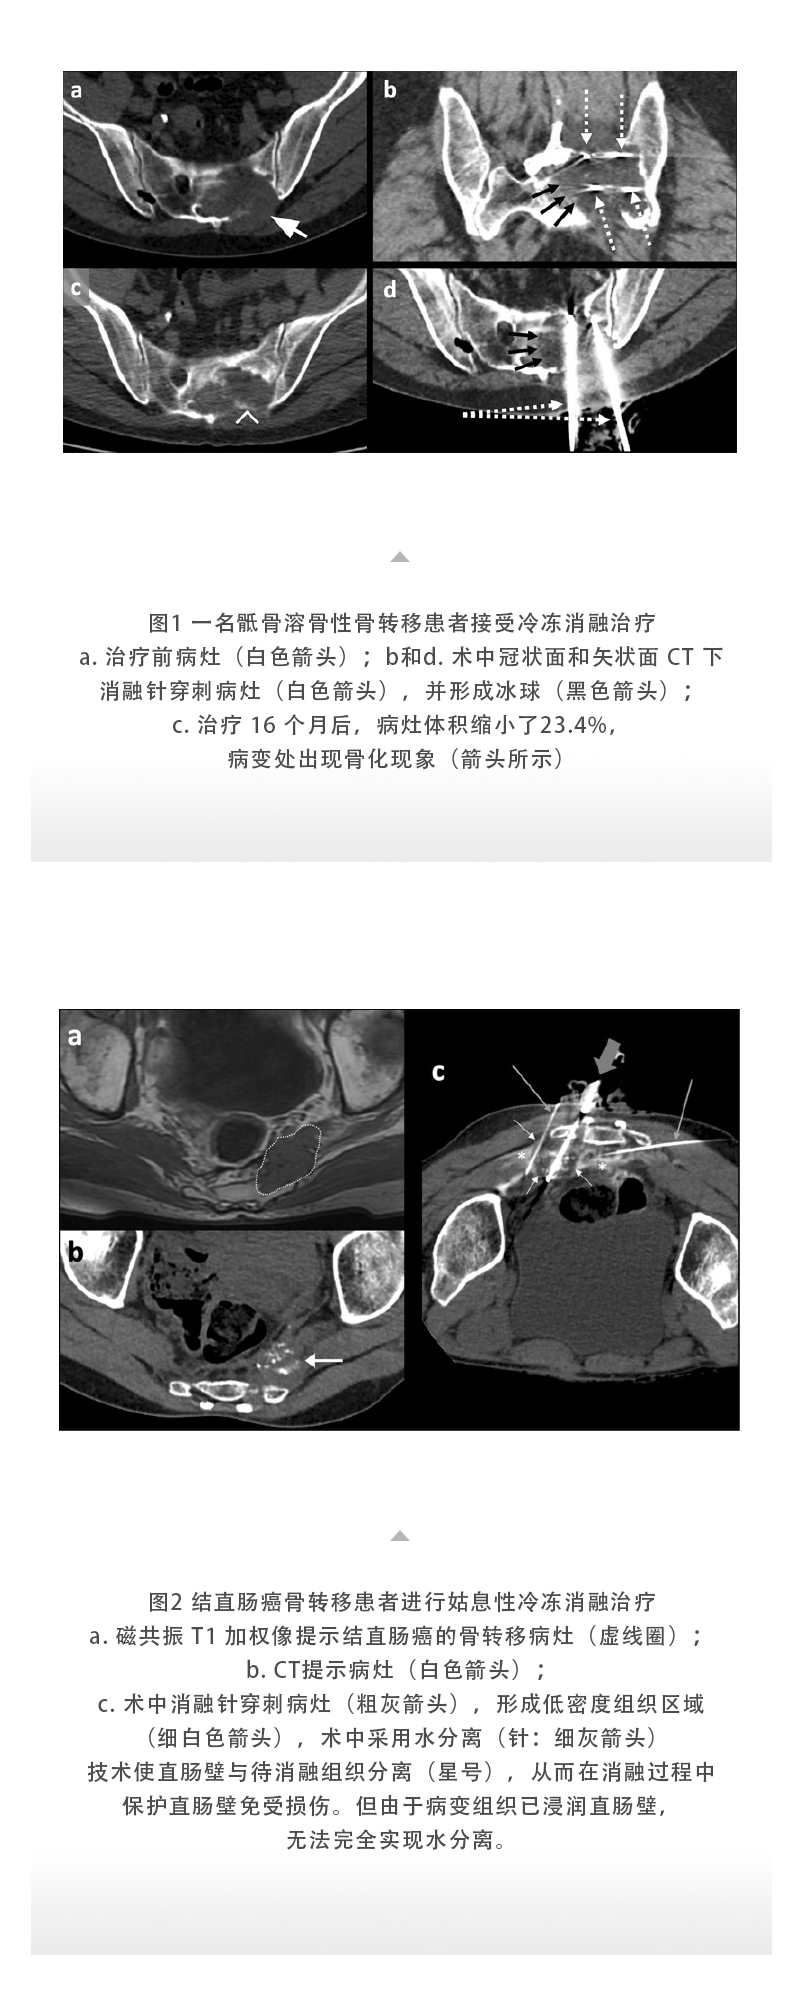

【HYGEA·科研資訊】骨腫瘤冷凍消融